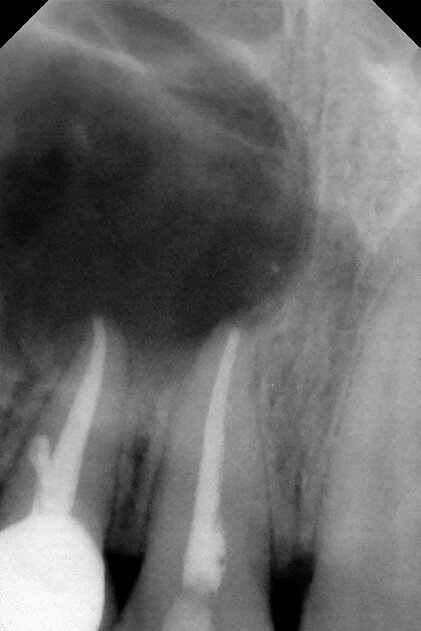

Figure 20: Periapical X-ray showing a 1.5 cm radiolucent lesion extending on apexes of teeth no 7 and 8 , note the lateral perforation on tooth no 7.

Figure 21: CAT view showing a radiolucent well circumscribed lesion with extended bone loss buccal, palatal and apical.

A 38 years-old female patient came to our clinic with swelling upper anterior area, she was medically fit with no health problems. The patient underwent an orthodontic treatment for 2 years and was about to remove it and place retainer. Intraoral examination showed swelling apical area of tooth no 7. The periapical x-ray and CAT view revealed a lateral perforation on the same mentioned tooth with a well circumscribed radiolucency in apical area (Fig.20, 21). Pain on percussion and slight mobility were noted. A surgical enucleation and extraction of tooth no 7 were conducted (Fig.22, 23, 24). 3 months postoperative CAT view shows an advanced horizontal bone loss with no recurrence of lesion in the area (Fig. 26), clinically after reflection of mucoperiosteal flap, the situation confirmed the CAT image (Fig.25) , the case was planned for PRF -associated bovine bone technique replacing the aggressive autologous bone graft procedure. After collection of PRF from patient blood culture, a first layer of L-PRF covering the bovine bone associated PRF complex (sticky bone) was done (Fig.27). The second layer of L-PRF came to cover the cross-linked collagen membrane (Fig. 28).